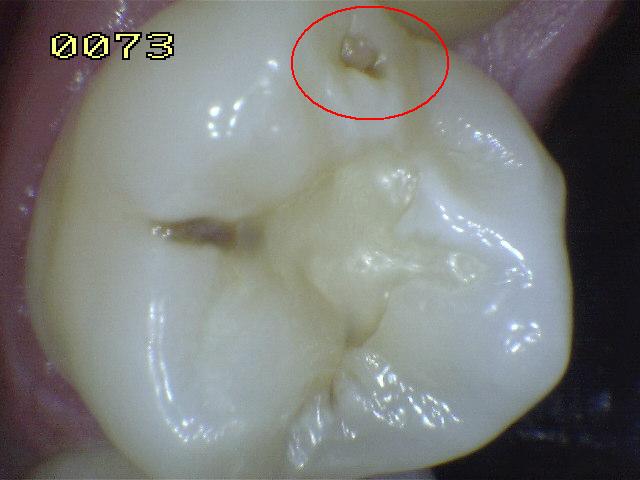

Código 5

(Caries Severa): Cavidad

detectable con dentina visible hasta la mitad de la superficie

-

Cavidad detectable

adyacente a la restauración/sellante con dentina visible

en el espacio de interfase con signos de caries tal como

se describe en el código 4, además de un espacio > 0,5

mm de ancho.

En los casos en que

los márgenes no son visibles, hay evidencia de pérdida

de continuidad en el margen de la restauración/sellante

y en la dentina, detectada por el paso de la punta de

0,5 mm de la sonda cuando se pasa por el margen de la

restauración/sellante.

Criterios para

determinar si la lesión es activa o detenida